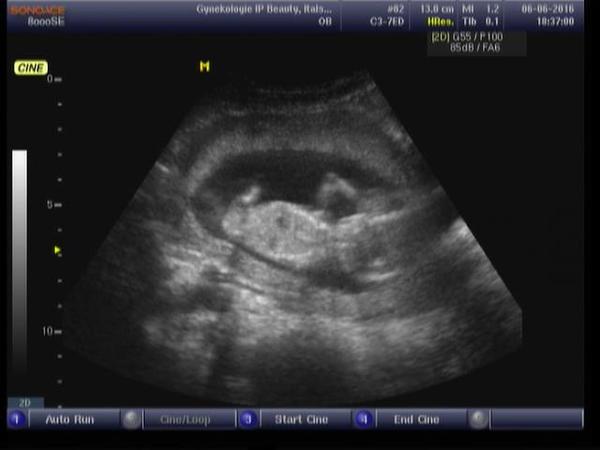

Je to holčička nebo chlapeček? Foto ultrazvuku

Ahoj maminky a budoucí maminky 😉 Prosím, poradila byste mi některá, co vidíte na fotce z ultrazvuku ve 20. týdnu za pohlaví? Určitě jste foteček viděly už mraky, proto vás žádám o radu...Nechci nikoho ovlivnit, proto svůj tip řeknu později 🙂 Děkuju moc!!!

@barbucha123 kluk🙂

@barbucha123 jasnej klucina

@barbucha123 urcite kluk